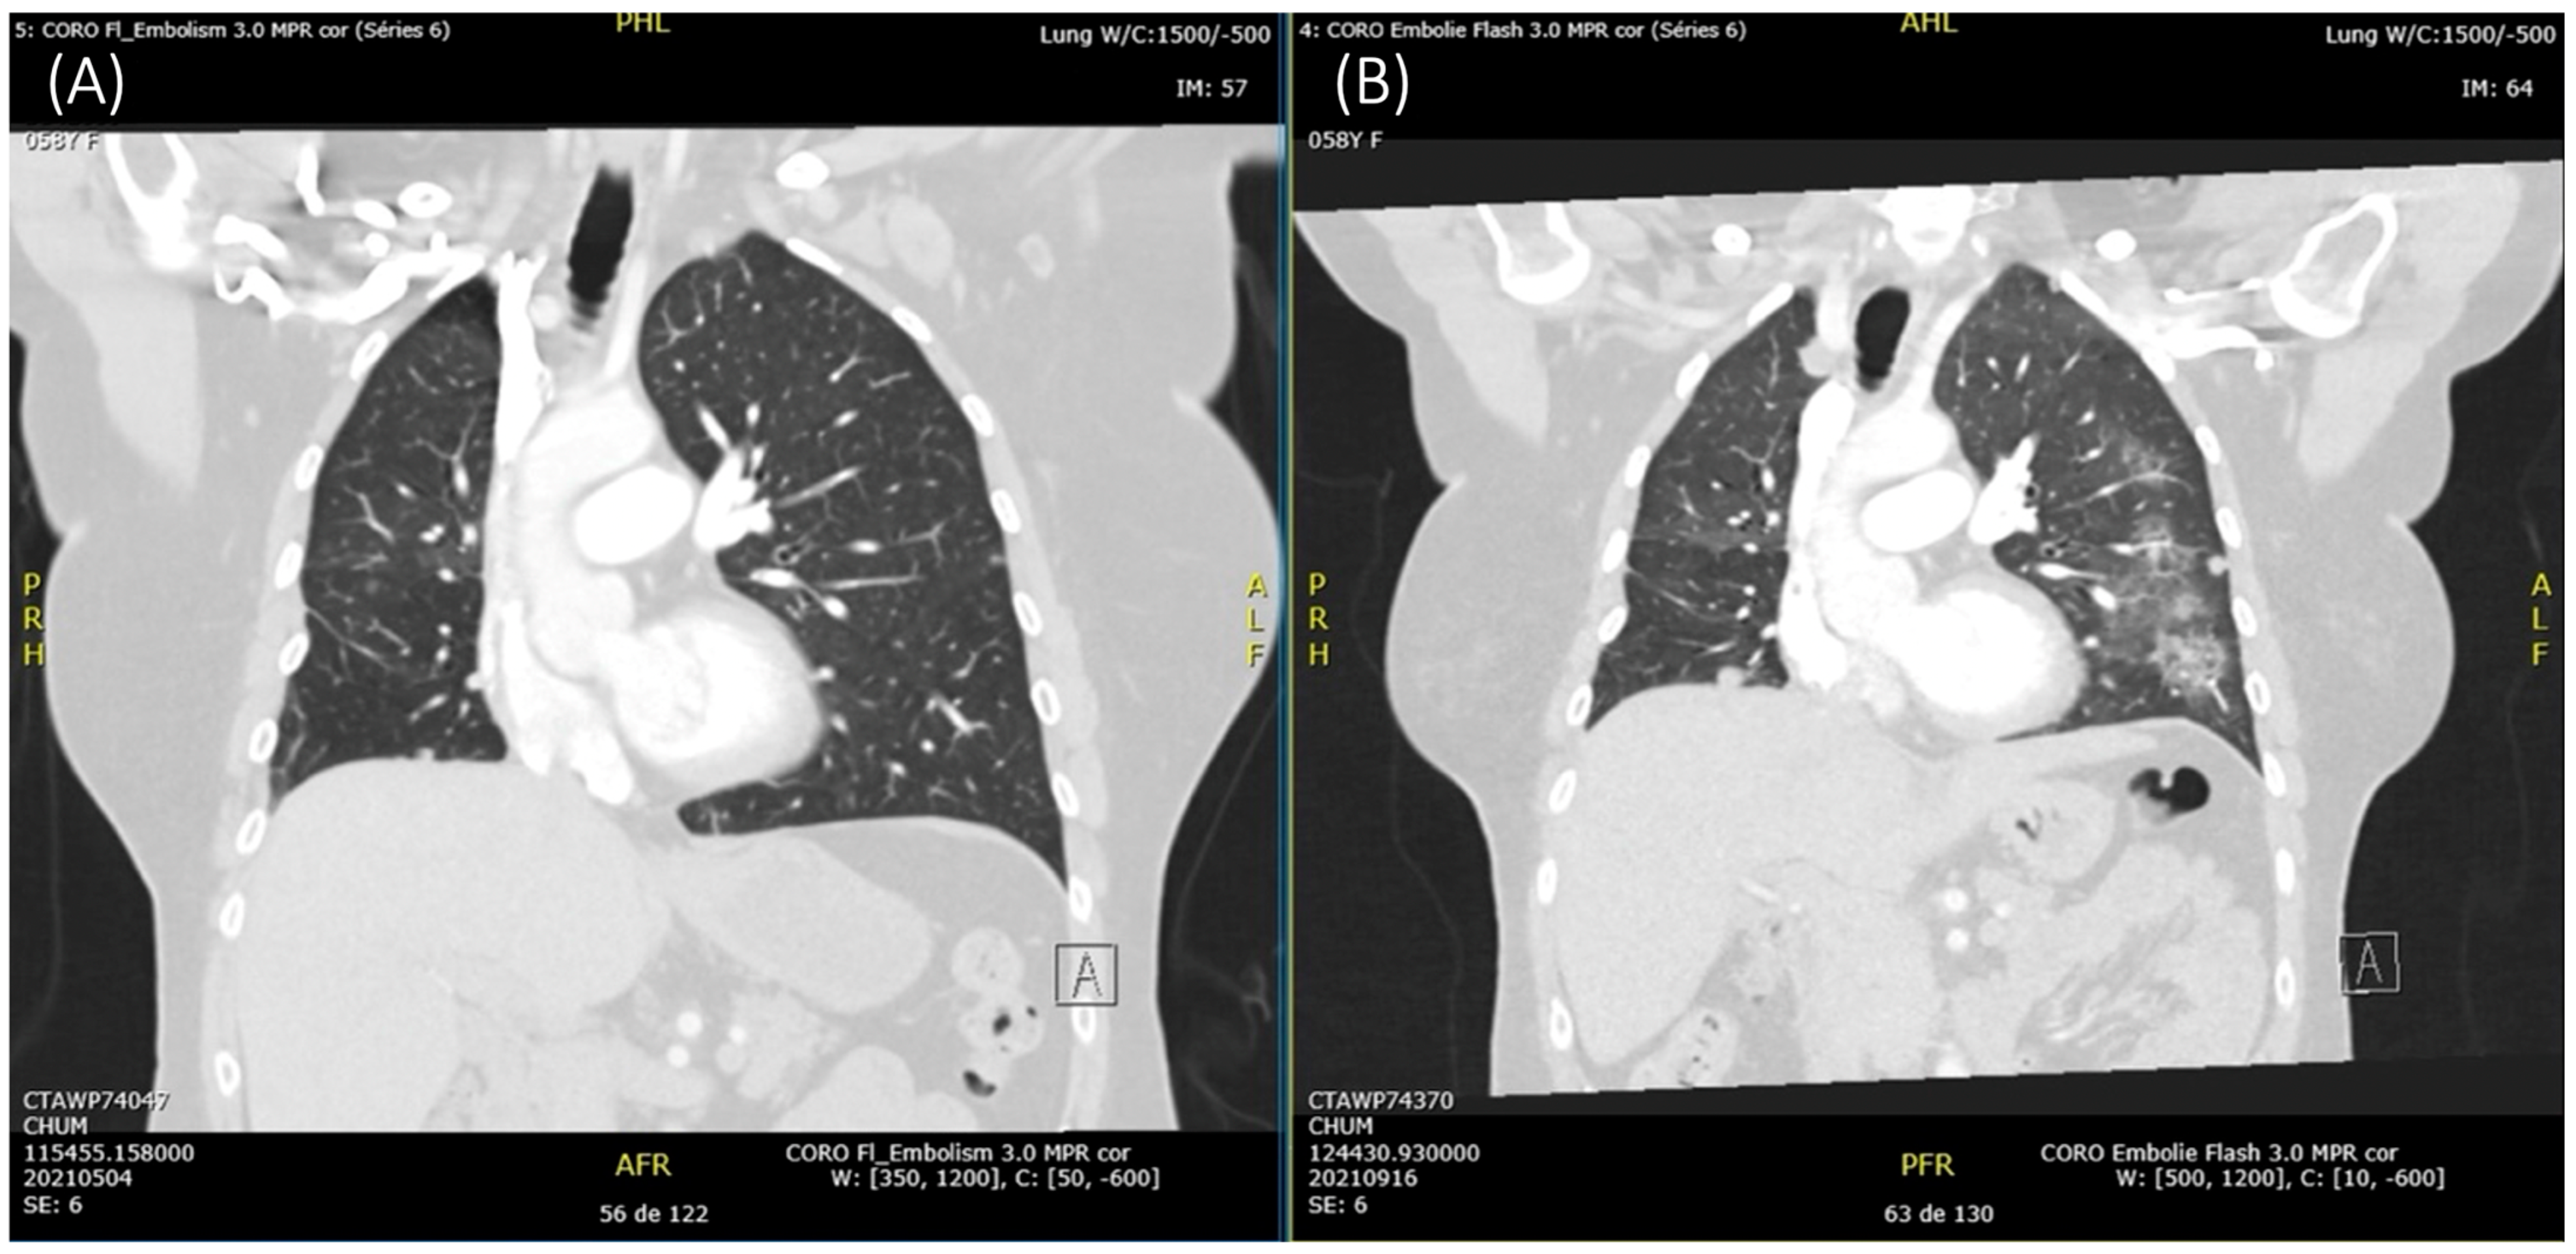

2. Case Description